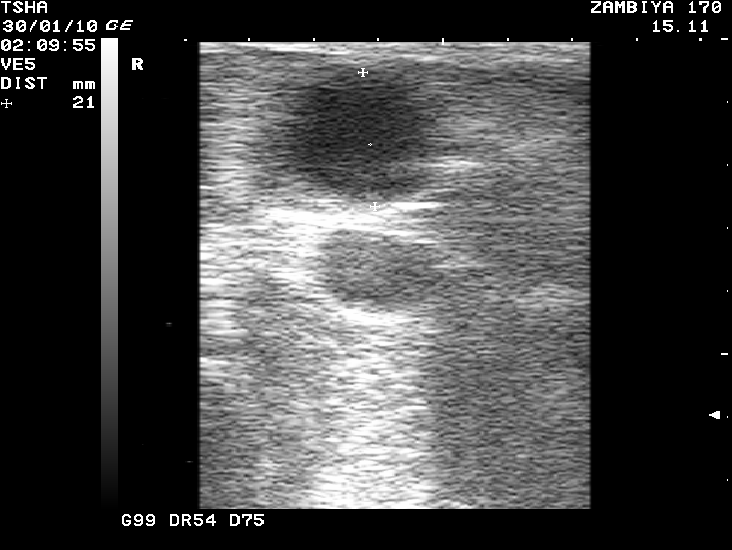

Рис. 3. Особенности восстановления овариальной функции у коровы Замбия 170 с фолликулярной кистой правого яичника. Овулин вводили 23.01.10 и 6.02.10. После первой гормональной обработки зафиксировали формирование фолликулярной кисты де ново в левом яичнике, после второй - формирование двух кистозных желтых тел в правом яичнике. Корова плодотворно осеменена в на 46 день от начала лечения (32 день после второй гормональной обработки).

Рис. 6. Вариабельность параметров фолликуло - и кистогенеза у коровы Фартовая 269 с хронической формой кистозной болезни яичников. Сканирование яичников проводили через каждые 14 дней

Пример отрицательного овариального ответа на овулин после первого курса гормонотерапии и восстановления овуляции после его повторного применения у коровы Замбия 170 проиллюстрирован на рис. 3.